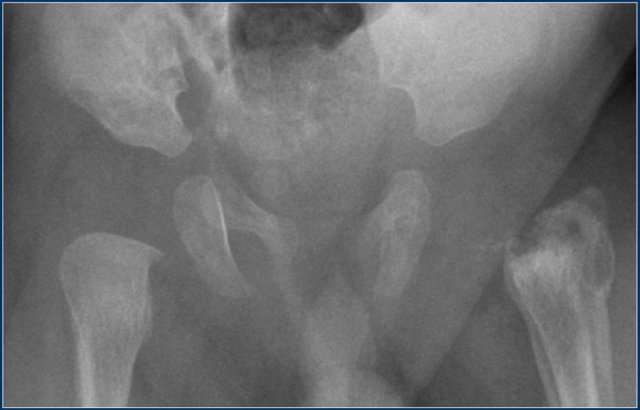

The images show Perthes disease of the right hip in a five-year old boy.

The findings are:

- Flattened and sclerotic femoral epiphysis.

- Subcondral fracture, best appreciated on the frog-leg lateral view.